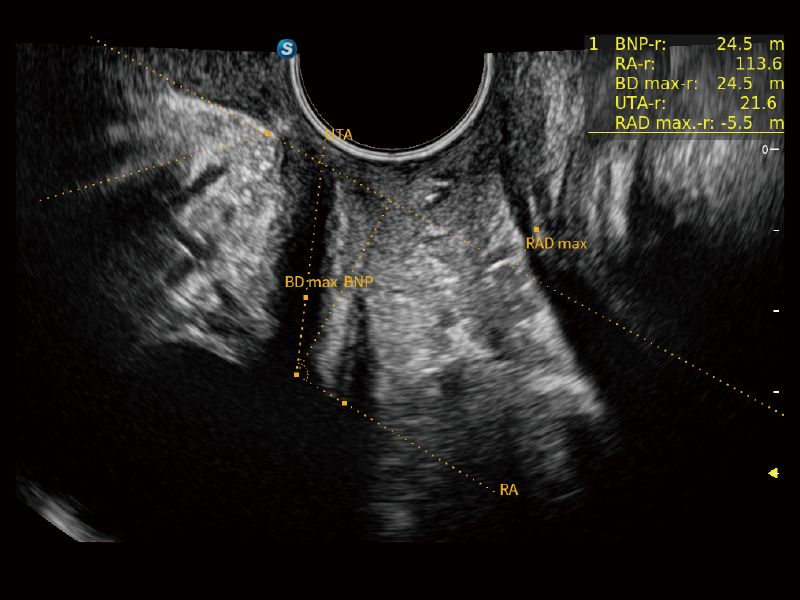

作为开立医疗全新打造的超高端旗舰超声产品,从探头抬起唤醒开启扫查到多维探头发射接收,通过先进的场成像发射、自适应聚合重建等技术,基于RF Data原始射频数据在图像生成、高端功能等方面实现突破,为妇产科、儿科提供全方位临床解决方案。

独有场成像发射技术

自适应聚合重建技术